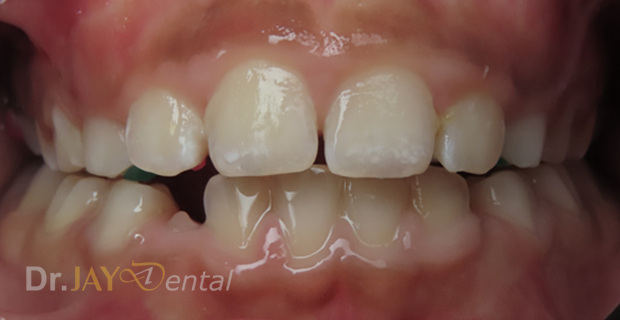

CASE 9

Complete crossbite of front/anterior teeth

Crossbite corrected in 10 months